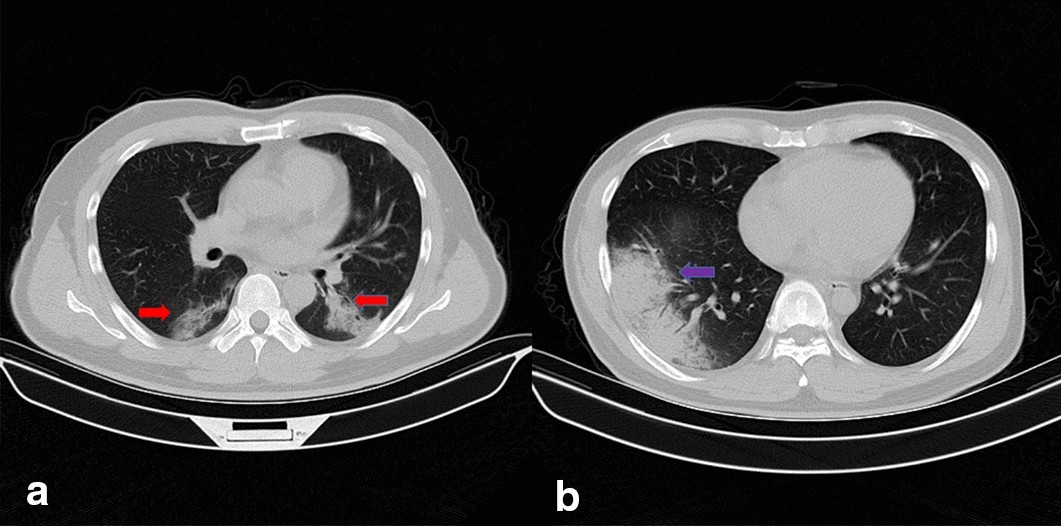

Fig. 1

Samples of COVID-19 and GP CT images. Picture a is the CT image of COVID-19 with bilateral GGOs while picture b is the CT image of GP with unilateral GGO. The red arrows point at the GGOs of COVID-19 and the blue arrow points at the GGO of GP